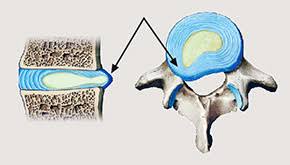

Die konservative Therapie eines Bandscheibenvorfalls umfasst eine. Antiphlogistika sind Medikamente die neben einer schmerzlindernden eine entzündungshemmende und abschwellende Wirkung haben. Bei der Schmerztherapie von Bandscheibenvorfällen kommen so genannte Antiphlogistika zum Einsatz.

43 699 17101871 praxisdr-unterhoferat. Man unterscheidet zwischen steroidalen und nicht-steroidalen Antiphlogistika NSAR wie Ibuprofen Diclofenac.